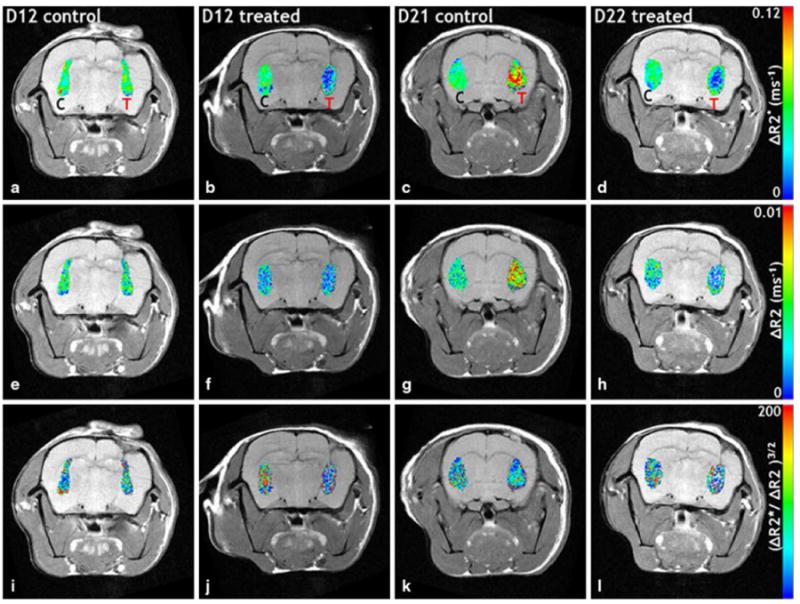

Representative in vivo MRI maps of ΔR2* (i.e. total blood volume), ΔR2 (i.e. microvascular blood volume), and (ΔR2*/ΔR2)3/2 (i.e. average vessel size) for tumor and contralateral ROIs are shown in Figure 2. Both the total (ΔR2*) and microvascular and (ΔR2) blood volume of the control tumor was comparable to that of the contralateral ROI at D12, but were markedly elevated at D21. In contrast, treated tumors exhibited lower blood volumes at both time points. The average vessel size for both tumor and contralateral ROIs were similar in the D12 control, but the vessel size in the treated D12 tumor was lower compared to the contralateral ROI. A similar effect on vessel size was not apparent at the later time point. Additionally, pooled histograms of ΔR2*, ΔR2, and (ΔR2*/ΔR2)3/2 from tumor and contralateral ROIs (Figure 3) show that for the D12 control group, the tumor and contralateral distributions were similar for all three in vivo MRI vascular parameters (Figure 3a-c), while for the D12 treated group, the distributions for all three parameters were shifted toward lower values (Figure 3d-f). In contrast, ΔR2* and ΔR2 were elevated in the control D21 tumors compared to the contralateral ROIs (Figure 3g-h). The treated D21 tumor exhibited ΔR2* and ΔR2 distributions that were shifted toward the lower contralateral values (Figure 3j-k). Both control and treated D21 tumors exhibited (ΔR2*/ΔR2)3/2 distributions similar to the contralateral ROIs.

Fig. 2.

In vivo MRI coronal slices of tumor-bearing rat brains. a–d (total blood volume), e–h ΔR2 (microvascular blood volume), and (i–l) (vessel size) maps of tumor (T) and contralateral (C) ROIs are overlaid on T2 w spin echo images. The total (a) and microvascular (e) blood volume for the control tumor is comparable to that of the contralateral ROI at D12, but is markedly elevated at D21 (c, g). Treated tumors exhibit decreased blood volumes at both time points. The tumor and contralateral vessel sizes were similar in the D12 control (i), but the vessel size in the treated D12 tumor was decreased (j) compared to the contralateral ROI. A similar effect on vessel size was not apparent at the later time point (l)